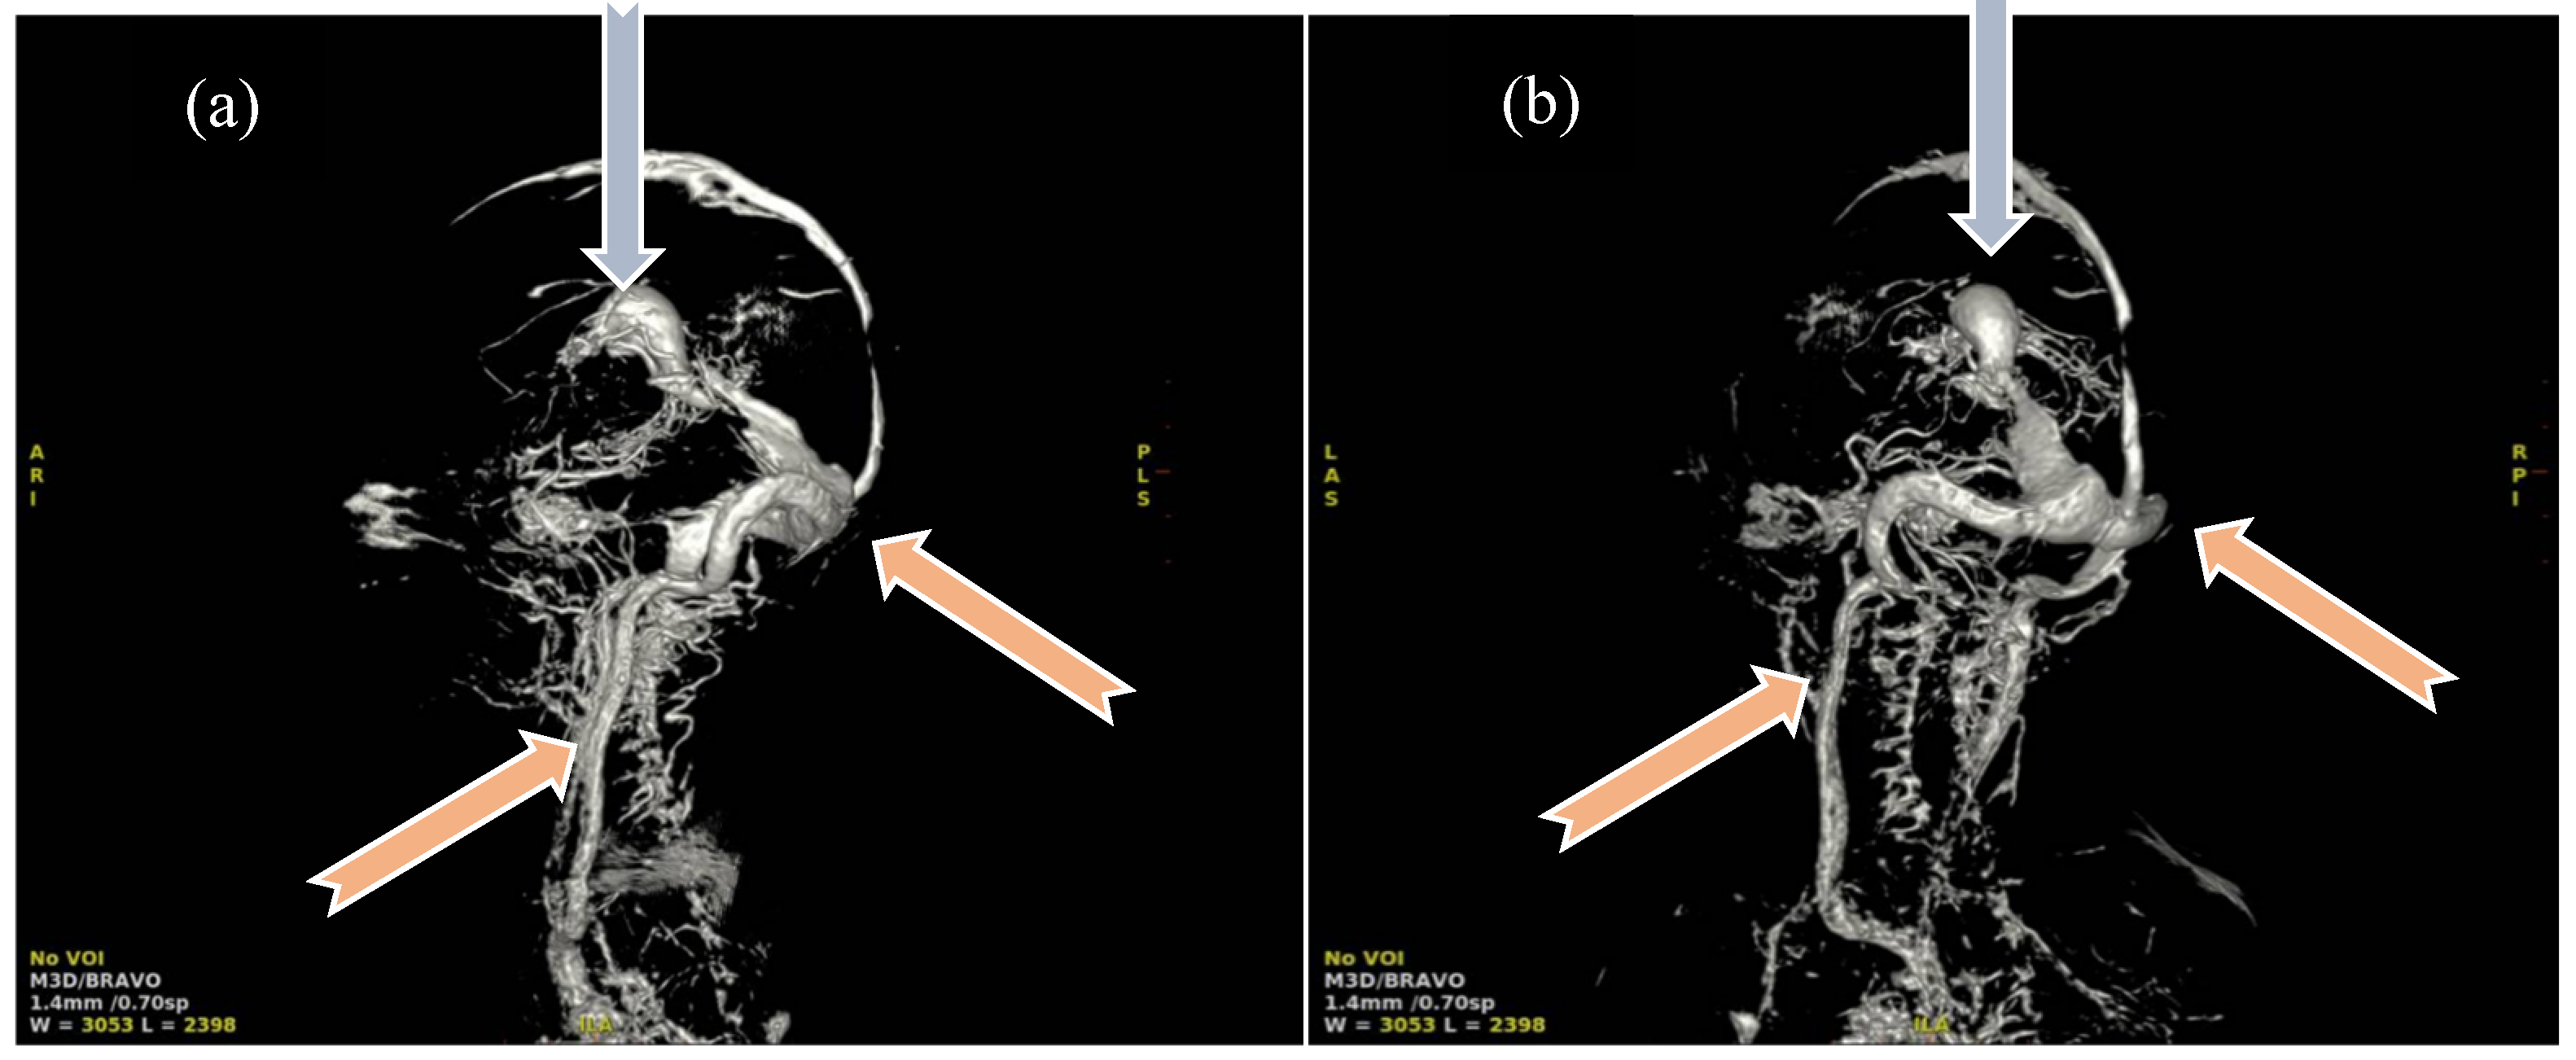

For some patients, the diagnosis was completed by brain MRI cerebral angio-CT (with iodinated radiocontrast agent at a concentration of 300 mg I/mL) methods for a better understanding of the Galen vein aneurysm morphology and its anatomical relations (see Figure 3, Figure 4, Figure 5 and Figure 6). Three of five patients who performed superior imaging techniques had large varieties of the Galen vein malformation, with variable degrees of compressive effect and secondary changes in the appearance of the midline and ventricular symmetry. Three patients presented with corpus callosum dysgenesis and three others with engorged arteries of the Willis polygon and enlarged pericerebral venous sinuses. None of the patients underwent an angiographic study of the arteriovenous malformation they had been diagnosed with in order to conceivably facilitate the perspectives of endovascular embolization in a center with expertise.

Figure 4. Angio-MRI sequence: Vascular aneurysmal dilation located at the level of the quadrigeminal tank (blue arrow), communicating with the large cerebral veins and the left middle cerebral artery, with collaterals emerging from the choroidal and posterior cerebral arteries—highly suggestive aspect of Galen vein aneurysm.

Figure 5. Three-dimensional reconstruction angio-MRI: (a) Sagittal view of the VoGM, (b) posteroanterior view in coronal plane. Aneurysmal median prosecephalic vein drained by the right sinus (blue arrows). Transverse/sigmoid sinuses and internal jugular veins of increased caliber (pink arrows). Multiple vascular pathways at the level of the basal nuclei connecting the anterior and posterior circulation. Carotid, vertebral arteries and basilar trunk exerting mass effect on the bulb.